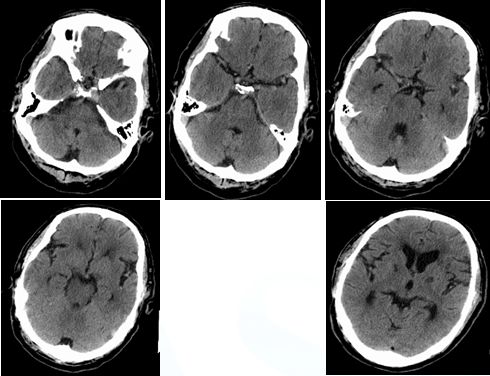

入院时颅脑CT(3.19)小脑梗塞

术后复查颅脑CT